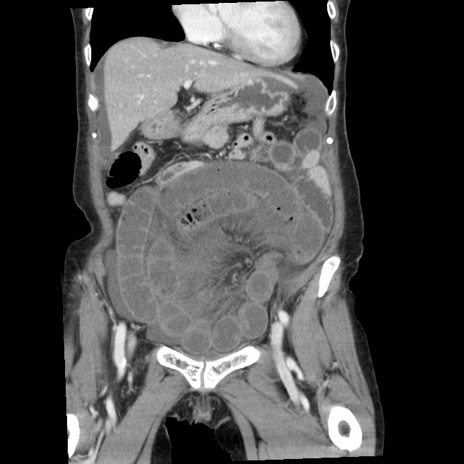

症例1(冠状断像)

【症例】80歳代女性

【主訴】腹痛

【現病歴】8時間前から腹痛あり来院。

【既往歴】糖尿病、脂質異常症、子宮体癌にて子宮全摘術

【身体所見】意識清明・会話良好だが腹痛で苦悶様、全腹部にわたって反跳痛と圧痛あり

【データ】WBC 13600、CRP 0.14、LDH 224、CK 90